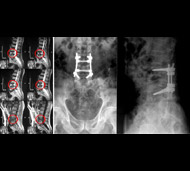

- Рентгенография. Медработники обычно проводят это исследование всем пострадавшим от травмы, у кого есть подозрение на повреждение спинного мозга. Рентген может выявить проблемы с позвонками, опухоли, переломы или дегенеративные изменения в позвоночнике.

- Компьютерная томография (КТ). КТ может предоставить лучшее изображение патологии, видимой на рентгеновских снимках. Этот вид обследования использует компьютер, чтобы воссоздать серию изображений поперечного сечения, которые могут выявить проблемы, связанные с костями, дисками и другие проблемы

- Магнитно-резонансная томография (МРТ). МРТ использует магнитную силу и радиоволны, чтобы воспроизвести изображения, полученные через компьютер. Этот тест очень помогает в ситуациях, когда необходимо рассмотреть спинной мозг и выявить грыжу межпозвоночного диска, сгустки крови и другие образования, которые могут сдавливать спинной мозг. Но МРТ нельзя проводить пациентам с сердечными водителями ритма или пострадавшим, которым необходима аппаратура, поддерживающая жизнедеятельность организма или приспособление для вытягивания шейного отдела позвоночника.

Цель операции – стабилизация позвоночника металлическими конструкциями (имплантантами). Наша клиника была первой в СНГ, кто применил современные конструкции при переломах позвоночника. Сейчас мы используем импортные конструкции типа CD Horison Legacy (США), Atlantis (США), Sextant (США), Socore (Франция). Операции требуют сложной рентгеновской техники и специального инструментария. При неосложненных переломах позвоночника больные могут ходить после таких операций уже на второй - третий день после операции. Также в Международном центре нейрохирургии впервые в Украине был внедрен метод миниинвазивных операций при переломах позвоночника.